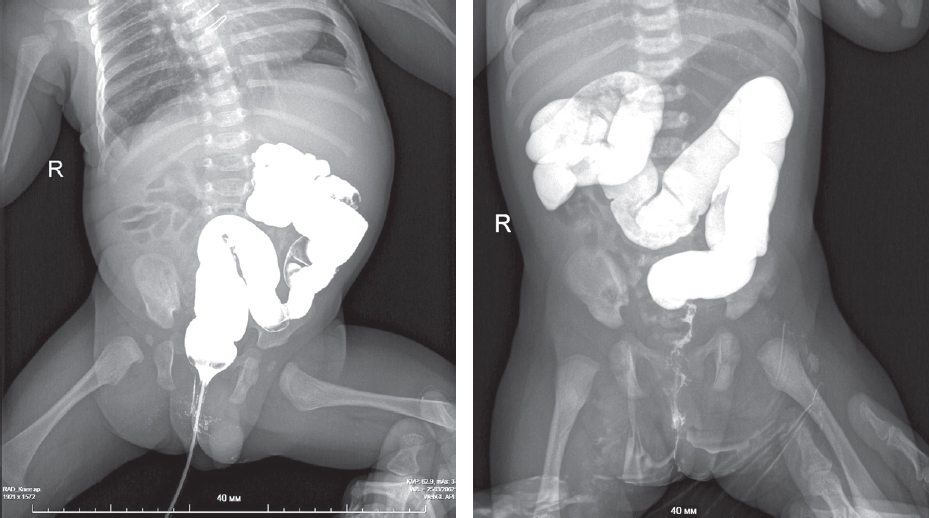

Из таблиц 1 и 2 следует, что наиболее часто встречающимися рентгенологическими признаками являлись левосторонне расположенная толстая кишка (30 %) и высокое стояние слепой кишки (39 %) (рис. 1).

Рис. 1. Левостороннее расположение толстой кишки (слева), высокое расположение слепой кишки (справа) у новорожденных, ирригография

Fig. 1. Left-sided location of the colon (left), high location of the cecum (right) in neonates, irrigography

В восьми случаях (18 %) левостороннее расположение толстой кишки сочеталось с атипичным расположением слепой кишки (высокое стояние или высокое и срединное положение) (рис. 2).

Рис. 2. Высокое и срединное положение слепой кишки у новорожденного, ирригография

Fig. 2. High and medial position of the cecum in a newborn, irrigography